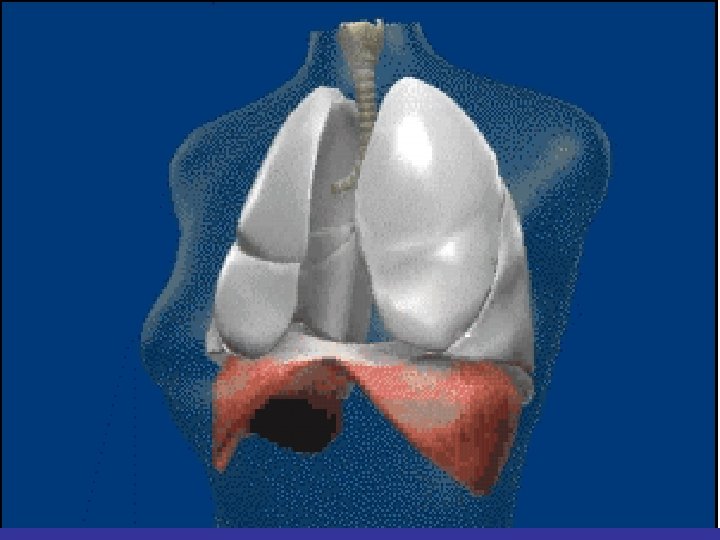

Lobes and Fissures